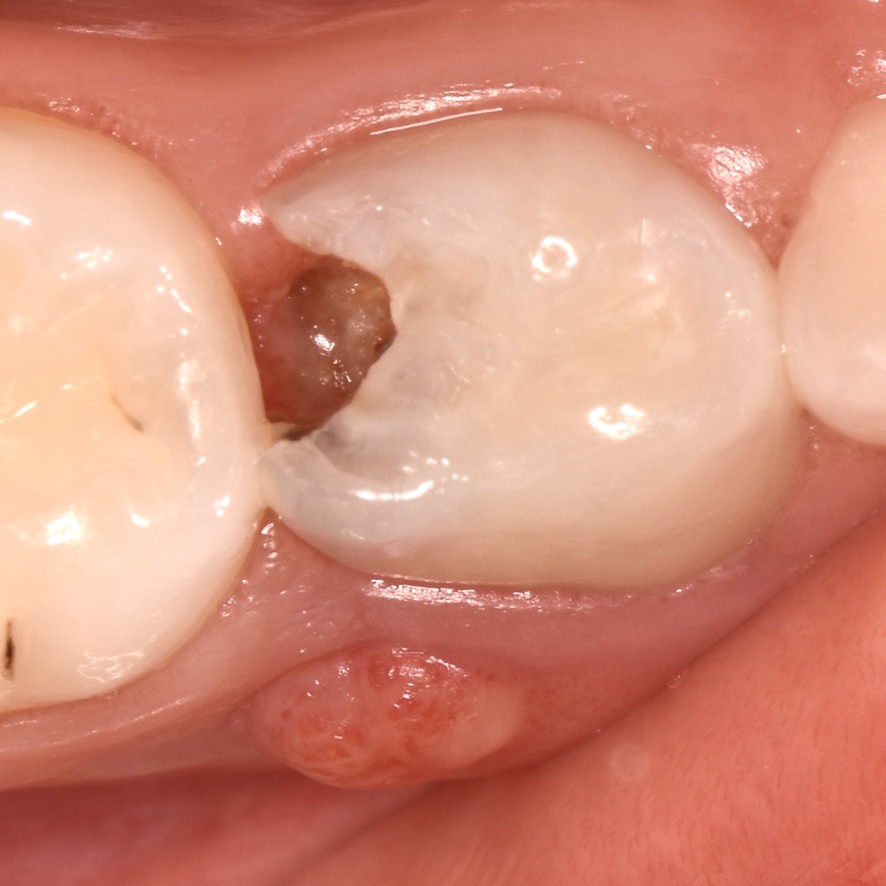

Imagen: diente de leche con lesión de caries y absceso periodontal por caries dental

Esta situación se puede complicar aún más cuando hay inflamación y presencia de abscesos. Es importante señalar que en los dientes de leche la progresión de lesiones de caries dental es más rápida que en los permanentes debido a la composición y estructura de este tipo de dientes.